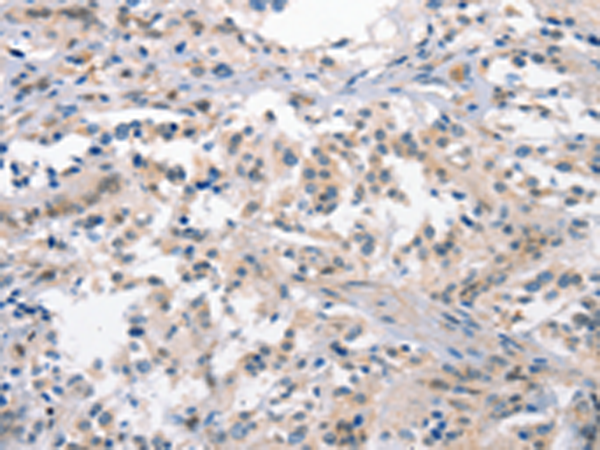

分类: 科研抗体货号: P04681别名: LOG15; 12-LOX; 15-LOX; 15-LOX-1应用: WB,IHC反应种属: Human, Mouse, Rat